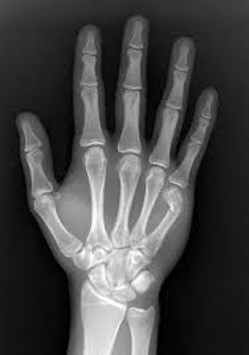

Often patients can still move their fingers with metacarpal fractures, so it is vital to get an x-ray to confirm the diagnosis.

Metacarpal head fracture |

Metacarpal neck fracture |